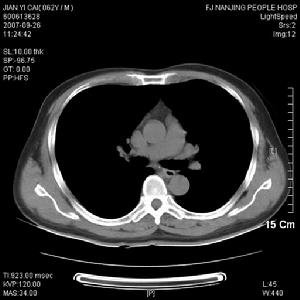

2、硬化型

(1)以顱面骨和顱底骨多見。

(2)表現為瘤骨密度非一致性增高,在硬化區內有散在的顆粒狀透亮區。

(3)顱骨穹隆的病。變常侵犯外板和板障,使骨骼膨大、增厚和囊性改變,呈磨玻璃樣或緻密硬化改變。

(4)面骨主要侵犯上頜骨,硬化區波及顳骨及眶下緣,並占據上頜竇腔。

4、位於顱底骨和面骨的病灶以硬化型多見,表現為骨密度均勻增高,骨質增厚,與正常骨分界可清楚不清。

骨纖維異常增殖症①變形性骨炎型:常為多骨型病變表現,其特點是顱骨增厚,顱骨外板和頂骨呈單側泡狀膨大,骨內板向板障和顱腔膨入,增厚的顱骨中常見局限和瀰漫的射線透明區和濃密區並存,這種骨吸收與硬化並存極似Paget變形性骨炎的表現。顱骨擴大和硬化,可從額骨擴大到枕骨。面部受累可導致眶和鼻腔狹窄及鼻竇腔消失,此型約占56%。②硬化型:此型多見上頜肥厚,可致牙齒排列不整,鼻腔、鼻竇受壓變小。上頜骨受累多於下頜骨,且多為單骨型。損害呈硬化或毛玻璃樣外觀。相反,下頜骨損害多見於多骨型,表現為孤立的骨壁光滑且可透過射線。此型約占23%。③囊型:顱骨呈孤立或多發的環形或玫瑰花形缺損,缺損從菲薄的硬化緣開始,其直徑可達數厘米。孤立的損害有似嗜酸性肉芽腫,多發的缺損可誤認為HandSchüllerChristian病,偶有數種X線類型出現於同一個體上。此型約占21%。套用CT或MRI檢查,能明確病變的位置和範圍,且能顯示與軟組織的聯繫。定期檢查可動態觀察病變的發展程度,對選擇術式進路、減少併發症和估計預後甚為重要。